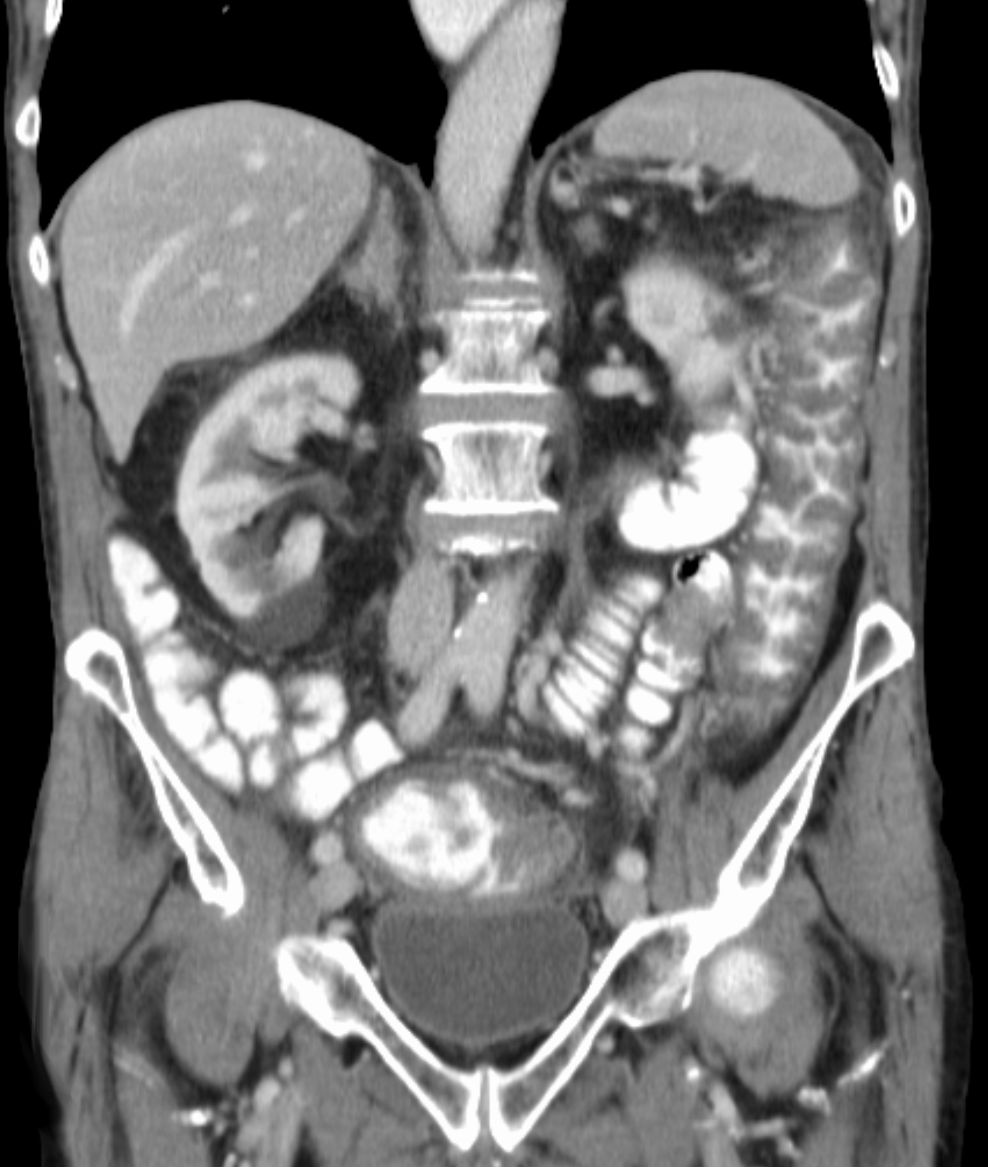

컴퓨터 단층 촬영에서 가성 막 대장염

''C. difficile'' 독소를 검출하는 검사가 나오기 전에는, 결장경 검사나 S상 결장경 검사를 통해 진단하는 경우가 많았다. 결장 또는 직장 점막에서 "가성 막"의 출현은 이 질환을 시사하지만, 진단적인 것은 아니다.[46] 가성 막은 염증성 잔해물과 백혈구로 구성된 삼출물로 이루어져 있다. 현재도 결장경 검사 및 S상 결장경 검사가 사용되기는 하지만, 현재는 ''C. difficile'' 독소 존재 여부를 검사하는 대변 검사가 진단의 첫 번째 단계로 자주 사용된다. 일반적으로 독소 A와 독소 B 두 가지만 검사하지만, 이 균은 다른 독소도 여러 개 생성한다. 이 검사는 100% 정확하지 않으며, 반복 검사에도 위음성률이 상당하다.[47]